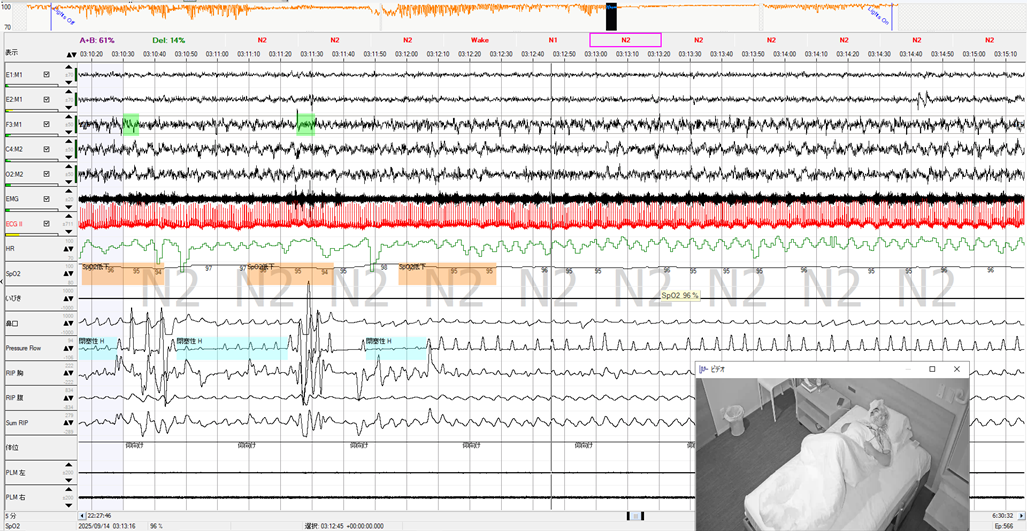

YUMINO'S コラム ゆみのPSGケースカンファ 学会・研究会 主要講演歴 著書出版歴 臨床研究 その他の活動 ゆみのPSGケースカンファ 2026年05月08日 記録前半は閉塞性呼吸イベントが主体で朝方CSR様の周期性呼吸を認めた症例 2026年05月01日 記録前半は閉塞性呼吸イベントが主体で朝方CSR様の周期性呼吸を認めた症例 2026年04月24日 超重症OSA症例の無呼吸と低呼吸 2026年04月14日 やせ型・若年者 でも重症のOSA症例 2026年04月10日 側臥位の就寝時間が長かったにも関わらず、重症の結果だったOSA症例 2026年04月03日 ノンレム睡眠側臥位の安定呼吸時の持続的なSpO2低下 2026年03月27日 CPAPタイトレーションで中枢性無呼吸が残存した症例 2026年03月13日 簡易検査結果と乖離して、大きく軽症化した症例 2026年03月06日 低振幅脳波で入眠判定が困難だったOSA症例 2026年02月27日 側臥位でも呼吸イベントが抑制されない重症OSAと徐波群発 1 2 3 4 5 年別 2026年 2025年 2024年 カテゴリー別